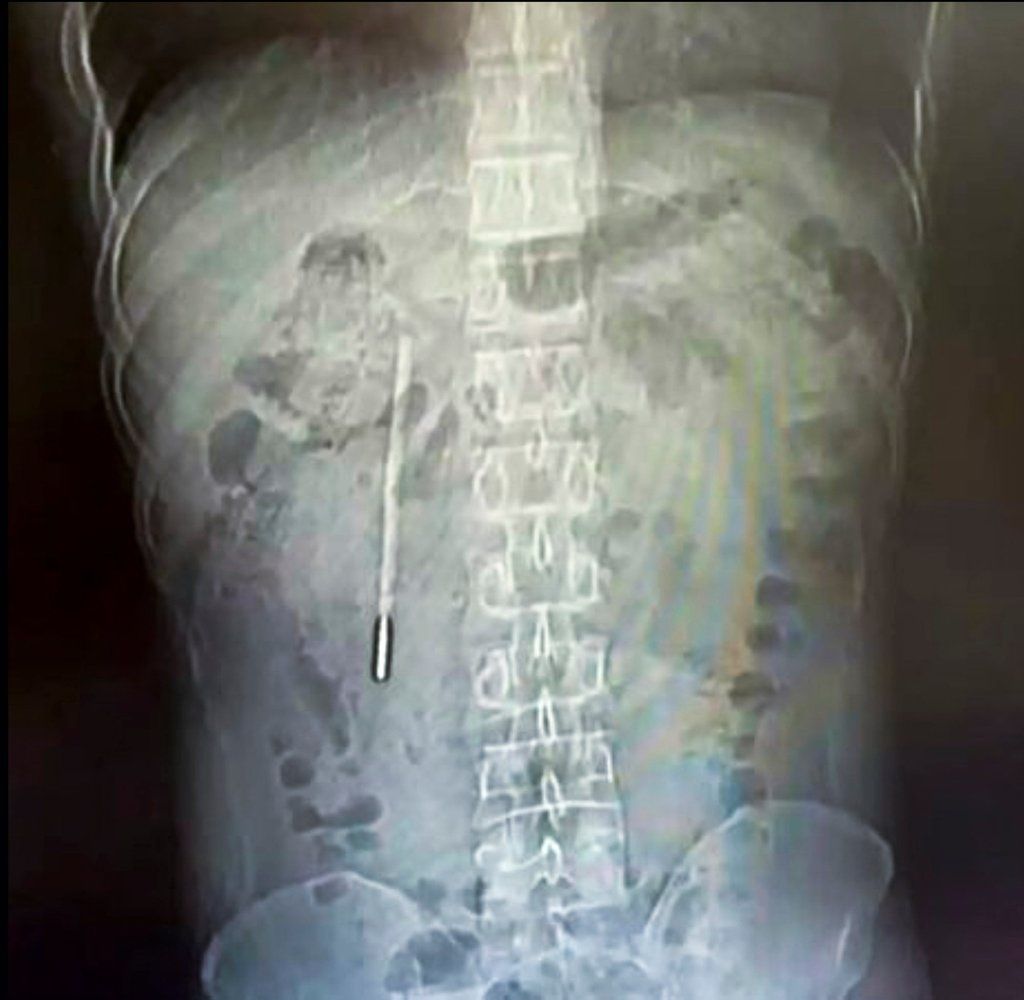

A scan revealed a foreign object in his duodenum, which doctors highly suspected to be a mercury thermometer.

As the tip of the thermometer was pressing directly against the intestinal wall, it posed a high risk of perforation and severe internal bleeding.